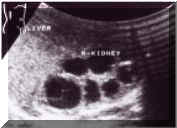

ADULT

POLYCYSTIC

KIDNEY

DISEASE

Sonography

easily

diagnoses

renal

by

revealing

numerous

cortical

cysts

of

varying

sizes,

often

with

irregular

margins.

Inracystic

infection

or

hemorrhage

may

cause

echogenic

debris

focal

calcification

in

the

wall

(Picture1).

Picture1.

Ultrasound

is

preferential

modality

to

establish

diagnosis.